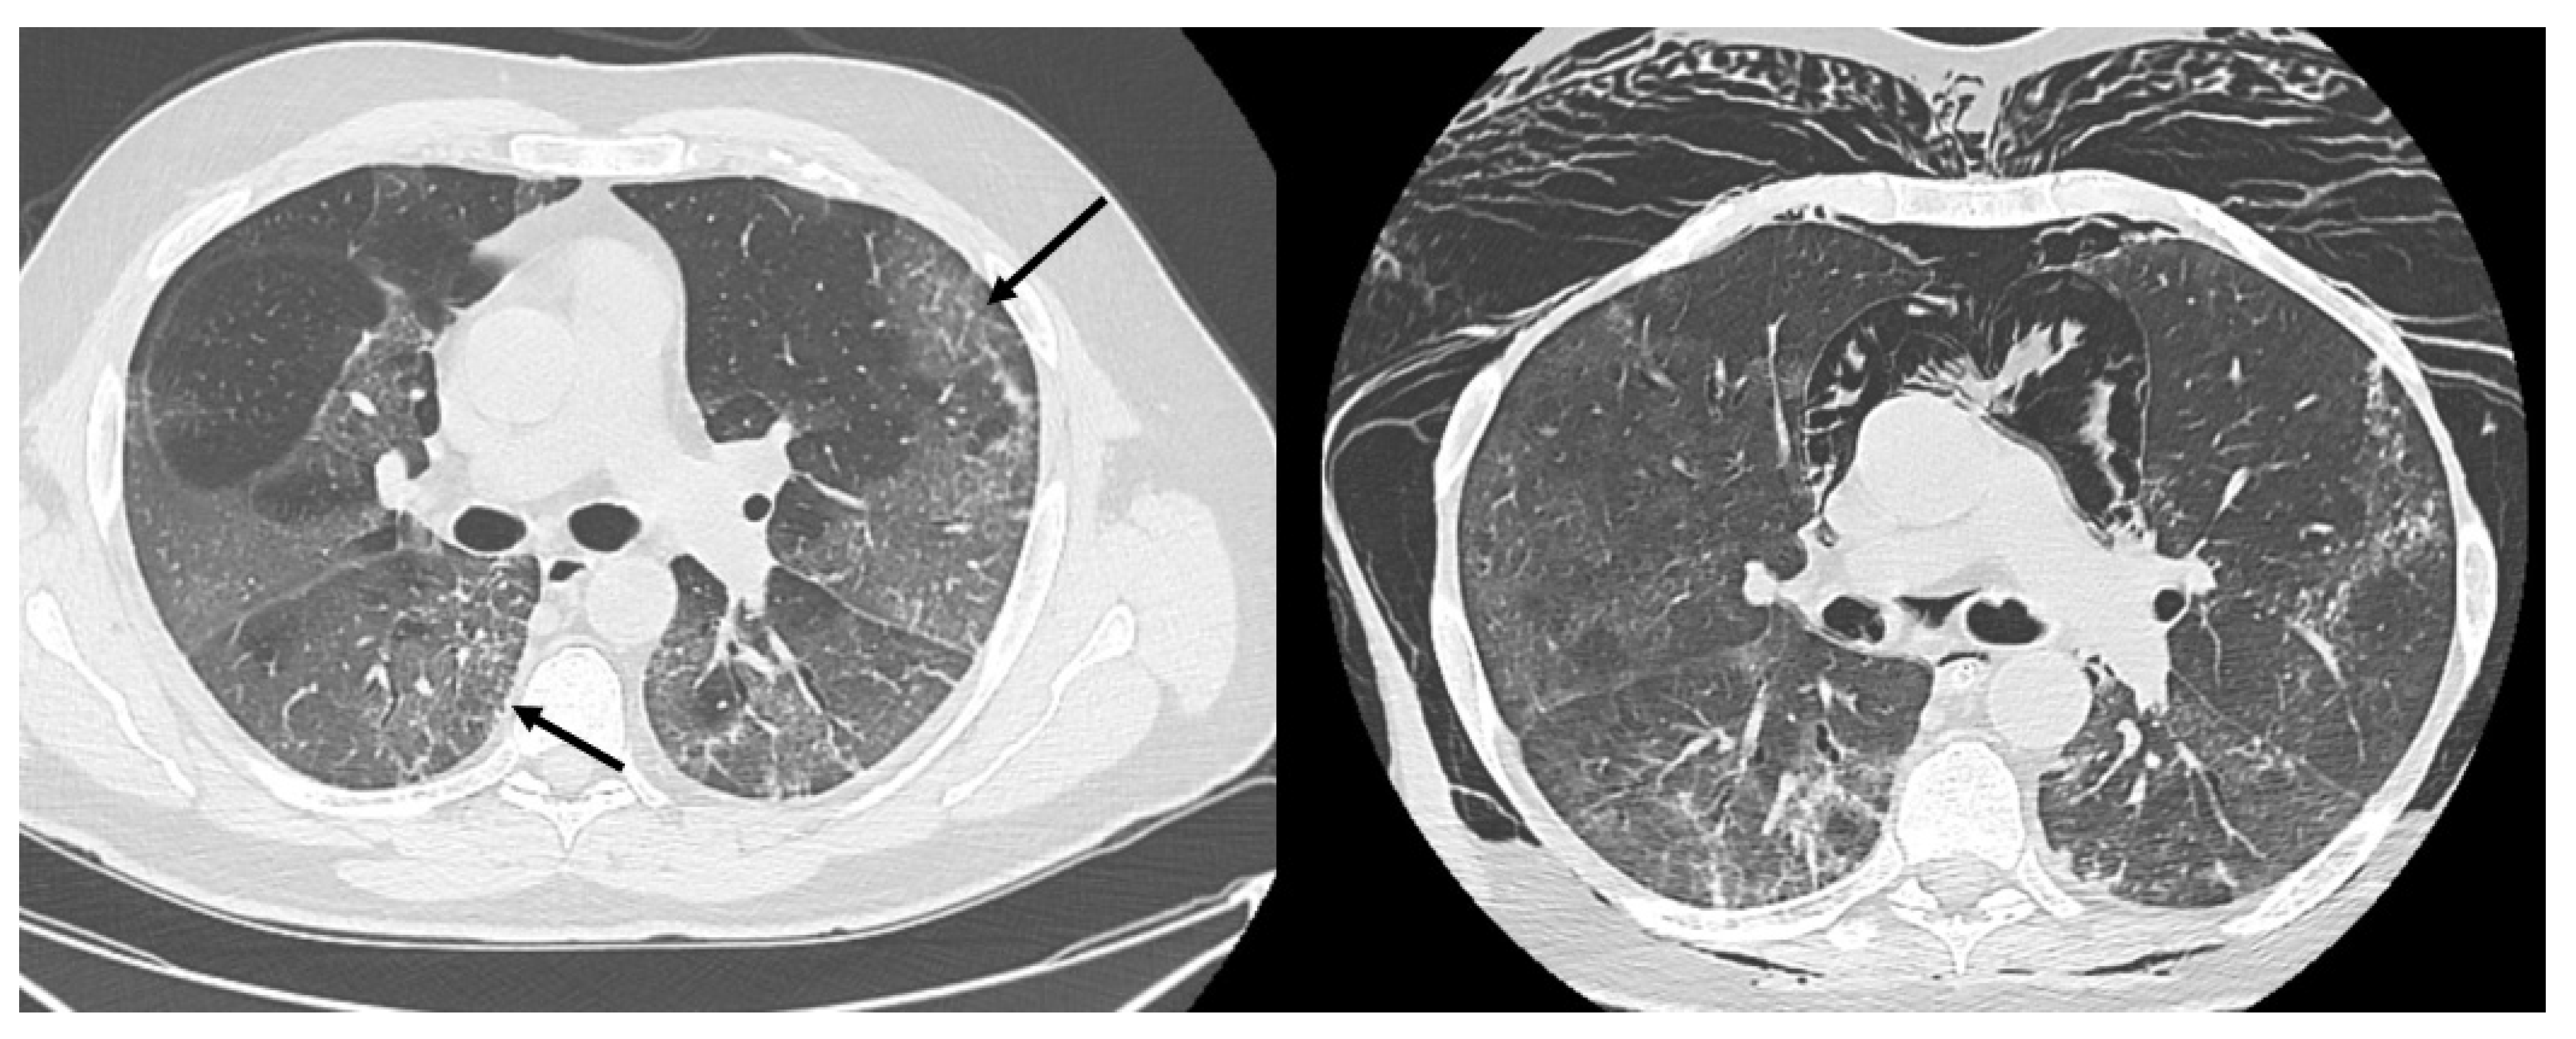

HRCT of the chest showed diffuse bilateral ground glass opacities (GGO) in all patients (Figure 1). Reticulation (Figure 2), traction bronchiectasis/bronchiolectasis (Figure 3), crazy paving and distortion (Figure 4) were observed in 29 patients (64%) at baseline. The total severity score was significantly higher at baseline in patients who eventually developed severe versus non-severe ARDS and pneumomediastinum/pneumothorax (16 versus 14; 95% CI 0.42 to 3.88; p = 0.01), as reported in Table 1. No other significant difference was observed at baseline.

Figure 1.

Diffuse bilateral ground glass opacities. Uneven distribution in the upper left lobe (arrow).